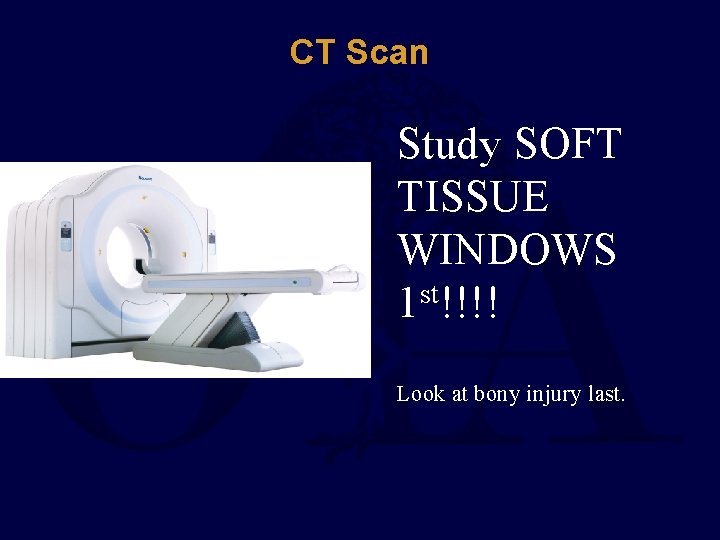

CT Scan Study SOFT TISSUE WINDOWS st 1 !!!! Look at bony injury last.

CT Scan – Soft Tissue Windows Air Densities = Open Fracture Hematoma=Morel-Lavallee